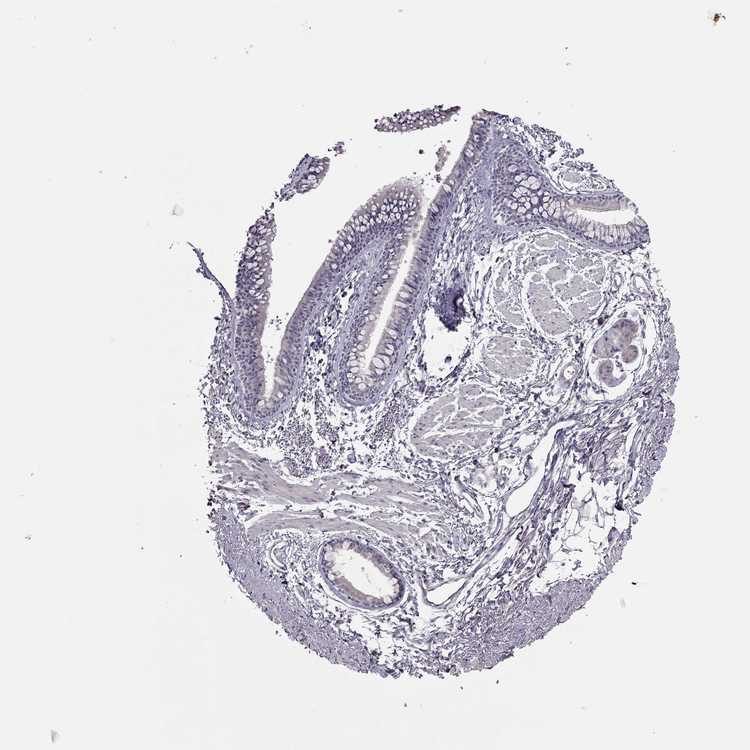

SOFT TISSUE 1 - Antibody stainingi

Antibody staining in the annotated cell types in the current human tissue is reported as not detected, low, medium, or high, based on conventional immunohistochemistry profiling in selected tissues. This score is based on the combination of the staining intensity and fraction of stained cells.

Each image is clickable and will lead to virtual microscopy that enables deeper exploration of all samples and also displays staining intensity scores, fraction scores and subcellular localization as well as patient and tissue information for each sample.

Antibody HPA063040

Fibroblasts Not detected

SOFT TISSUE 2 - Antibody stainingi